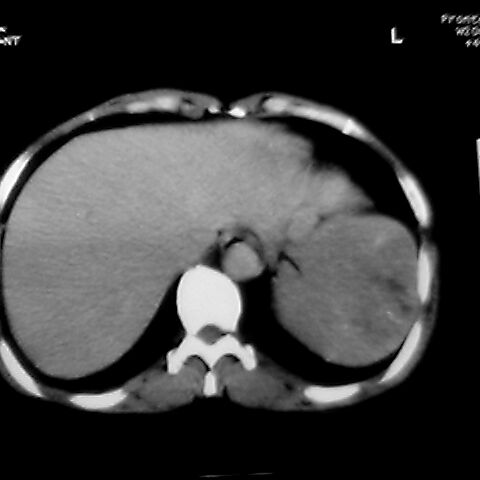

女 48岁 食道癌术前体检发现脾占位。

脾胀内部巨大低密度肿块,边界清或不清,中心坏死,轻度增强,内见散在钙化,结合食道癌病史多考虑:转移癌.

1肝右下叶小囊肿2右肾上极囊肿或错构瘤3脾脏不典型血管瘤可能性大.

脾脏低密度灶伴钙化,增强化明显,中心见液化坏死灶,强化延时明显。考虑血管瘤。转移瘤待排。

右肾见类圆形低密度影.结合病史.脾及右肾转移性ca可能性大

1,脾血管瘤。2,右肝,右肾小囊肿。